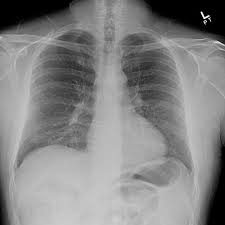

भोपाल में हाइपर सेंसटिव न्यूमोनाइटिस के मरीजों में तेजी से बढ़ोतरी, कबूतरों से फैल रही फेफड़ों की गंभीर बीमारी

भोपाल। प्रदेश में हाइपर सेंसटिव न्यूमोनाइटिस के मामलों में चिंताजनक वृद्धि दर्ज की जा रही है। सरकारी अस्पतालों के आंकड़ों के मुताबिक, रोजाना 20 से 25 संक्रमित मरीज इलाज के लिए पहुंच रहे हैं, जिनमें से करीब 25 प्रतिशत मरीजों को गंभीर हालत में भर्ती करना पड़ रहा है।

विशेषज्ञों का कहना है कि यह बीमारी मुख्य रूप से कबूतरों के पंख और उनकी बीट में मौजूद सूक्ष्म कणों के कारण फैलती है। ये कण हवा के माध्यम से सांस के जरिए फेफड़ों में पहुंच जाते हैं और वहां पर गंभीर एलर्जी व सूजन पैदा कर देते हैं।

हाइपर सेंसटिव न्यूमोनाइटिस बीमारी का अभी कोई स्थायी इलाज नहीं है। एक बार फेफड़ों में स्थायी नुकसान हो जाने पर मरीज की सांस लेने की क्षमता घट जाती है और जीवनभर तकलीफ बनी रह सकती है।